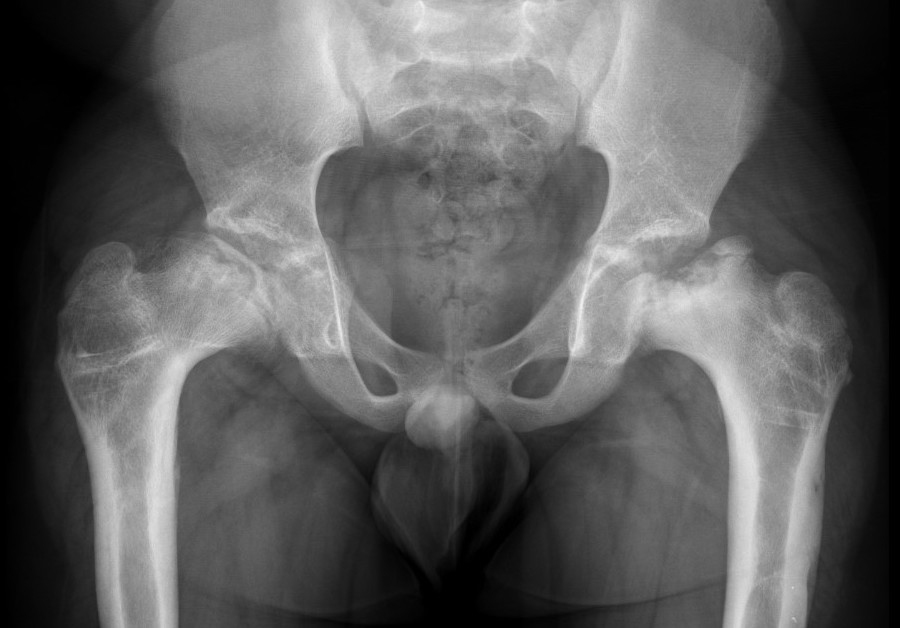

Uncontained hip / lateral extrusion

Hinge abduction